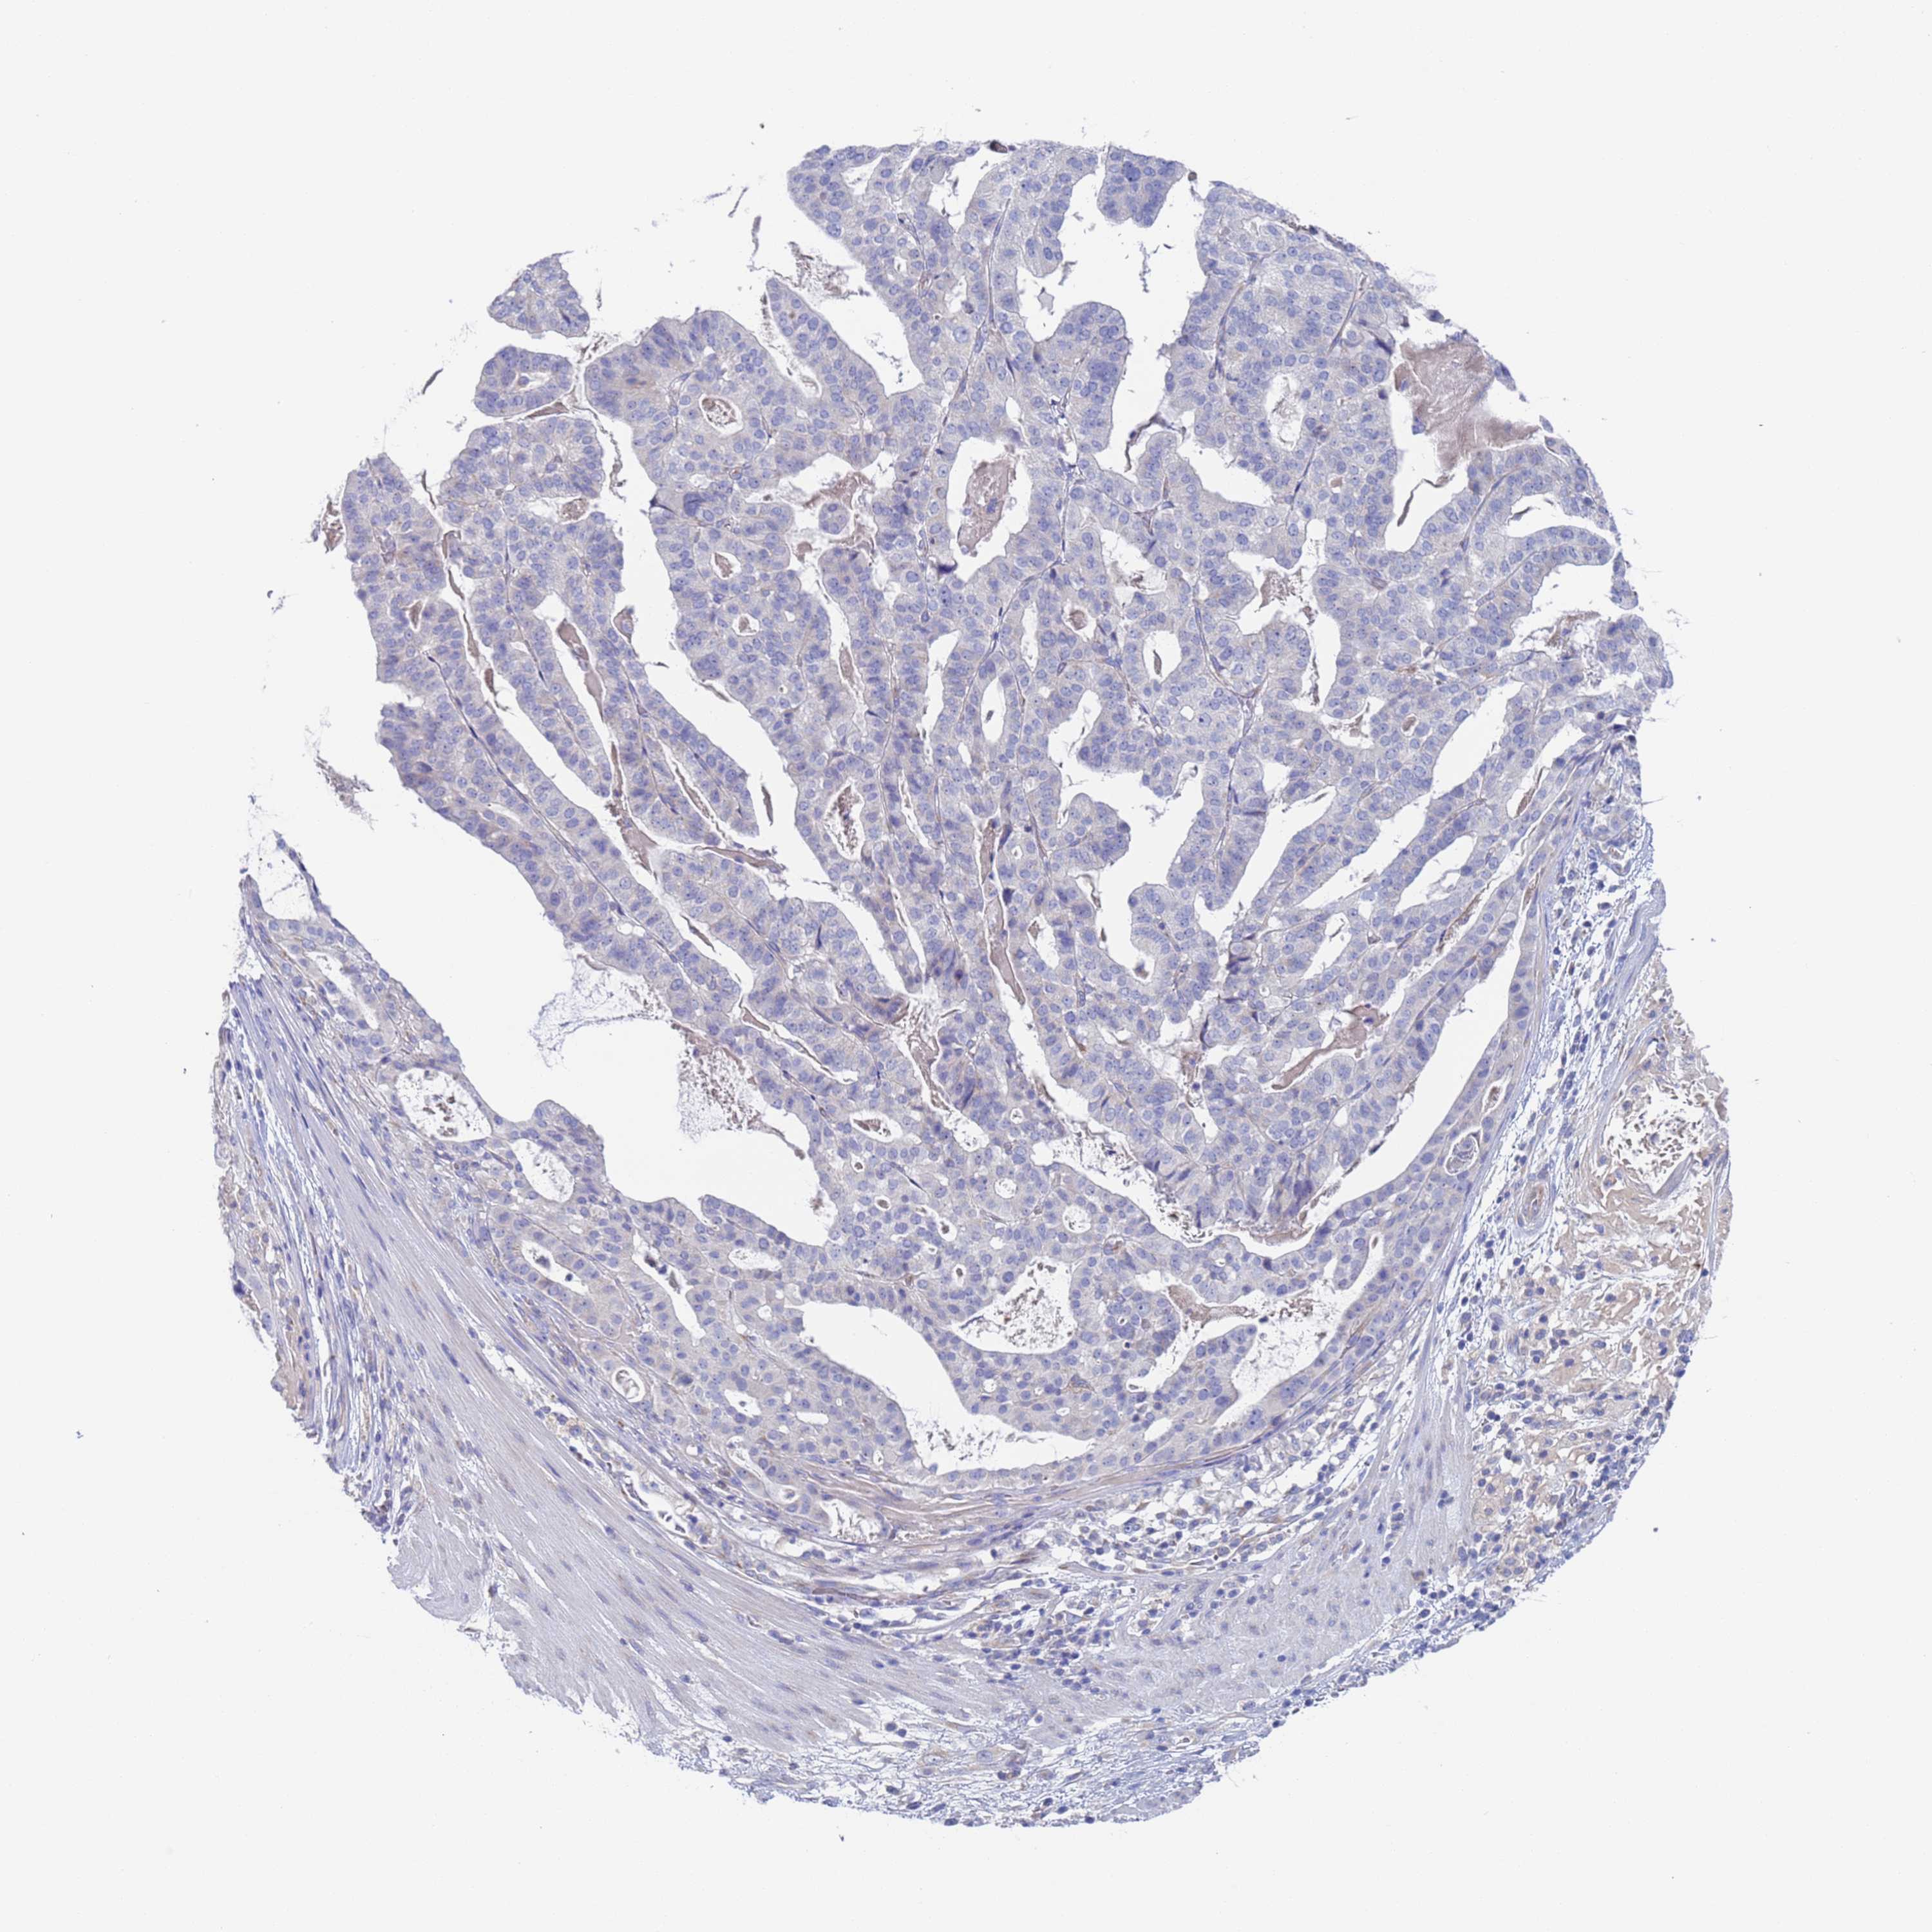

STOMACH CANCER - Protein expressioni

A mouse-over function shows sample information and annotation data. Click on an image to view it in a full screen mode. Samples can be filtered based on level of antibody staining by selecting one or several of the following categories: high, medium, low and not detected. The assay and annotation is described here.

Note that samples used for immunohistochemistry by the Human Protein Atlas do not correspond to samples in the TCGA dataset.

Antibody stainingi

Antibody staining in the annotated cell types in the current human tissue is reported as not detected, low, medium, or high, based on conventional immunohistochemistry profiling in selected tissues. This score is based on the combination of the staining intensity and fraction of stained cells.

Each image is clickable and will lead to virtual microscopy that enables deeper exploration of all samples and also displays staining intensity scores, fraction scores and subcellular localization as well as patient and tissue information for each sample.

Antibody HPA047716

Staining

High

Medium

Low

Not detected

Intensity

Strong

Moderate

Weak

Negative

Quantity

>75%

75%-25%

<25%

None

Location

Nuclear

Cytoplasmic/membranous

Cytoplasmic/membranous,nuclear

Adenocarcinoma, NOS